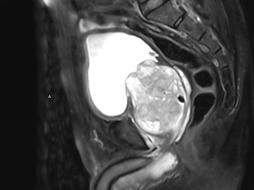

68岁的张大爷(化名)十多年来一直排尿不顺畅,夜尿频繁,逐年加重。两年前,排尿时开始感到下腹部疼痛。近期出现了排尿中断的情况,有时还伴随尿痛。在家人的陪伴下,张大爷来到我院泌尿外科就诊。

经检查,患者前列腺体积大小达到200ml,与蟠桃相当,而正常前列腺仅20ml,且合并巨大膀胱结石,这正是导致其症状加重的主要原因。

入院后,泌尿外科团队为其完善相关检查,排除手术禁忌症后,包卿兵主任带领团队经详细讨论与术前评估,考虑患者前列腺体积过大,传统的电切手术风险较高且可能出血较多,决定为其实施“经尿道前列腺钬激光剜除术+经尿道膀胱结石钬激光碎石术”。